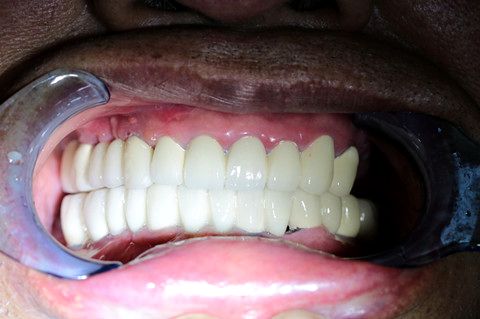

义齿戴入口腔内的情况